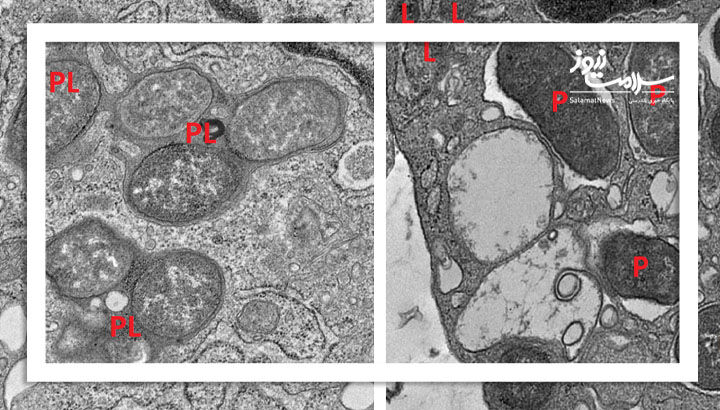

در آزمایشهای انجامشده روی موشهای فاقد GIV، تماس با باکتریهای روده باعث التهاب شدید، ضخیم شدن دیوارهی روده و زخمهای مشابه کرون شد. برخی از این موشها حتی دچار سپسیس (عفونت گستردهی خون) شدند.در مقابل، موشهای سالم که این دو پروتئین را داشتند، توانستند تعادل ایمنی خود را حفظ کنند.

این یافته با آزمایشهای میکروسکوپی و مدلهای حیوانی تأیید شد و نشان داد قطع ارتباط بین GIV و NOD2 زنجیرهای از التهاب بیپایان را ایجاد میکند.